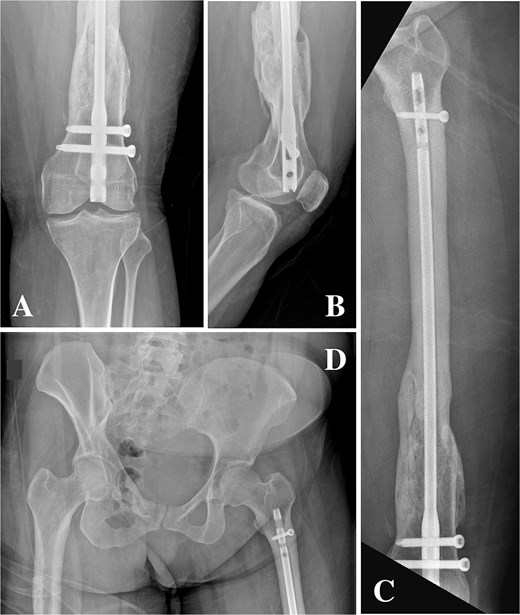

On clinical examination, the left thigh was swollen and ecchymotic with visible deformity. Passive and active range of motion at the hip and knee was markedly restricted due to pain. Distal neurovascular function was intact. All laboratory investigations were negative or normal. Radiographs of the femur, hip, and knee revealed a hypertrophic malunion at the distal femur with a proximal periprosthetic fracture and an intramedullary nail inserted (Fig. 1). A preoperative non-contrast computerized tomography (CT) scan of the left thigh confirmed an old distal femoral fracture with in situ fixation and extensive hypertrophic callus. Multiple small free bone fragments were seen in the distal thigh. The hardware extended beyond the distal and medial cortical margins, with screws also breaching the cortex. An oblique fracture line was noted proximally adjacent to the proximal screw, without displacement. No soft tissue hematoma or joint effusions were identified (Fig. 2). The patient was admitted for surgical management. Revision antegrade nailing was performed intraoperatively. Upon removal of the retrograde nail it was confirmed to be an antegrade construct (Fig. 3). A correctly sized antegrade femoral nail was inserted via the proximal entry point under fluoroscopic guidance. Postoperative imaging demonstrated satisfactory alignment and stable fixation. At follow-up, the patient reported improved mobility and reduced pain. Radiographs showed signs of progressive healing. No signs of infection, implant loosening, or neurovascular compromise were observed (Fig. 4).

(A, B) Anteroposterior and lateral radiographs showing hypertrophic non-union of the distal femur with retained intramedullary nail and locking screws. (C) Anteroposterior view demonstrating a femoral nail inserted via a distal entry point with abnormal proximal extension. (D) Anteroposterior pelvis radiograph showing the antegrade-design nail extending proximally from a retrograde entry point, terminating proximal to the lesser trochanter.